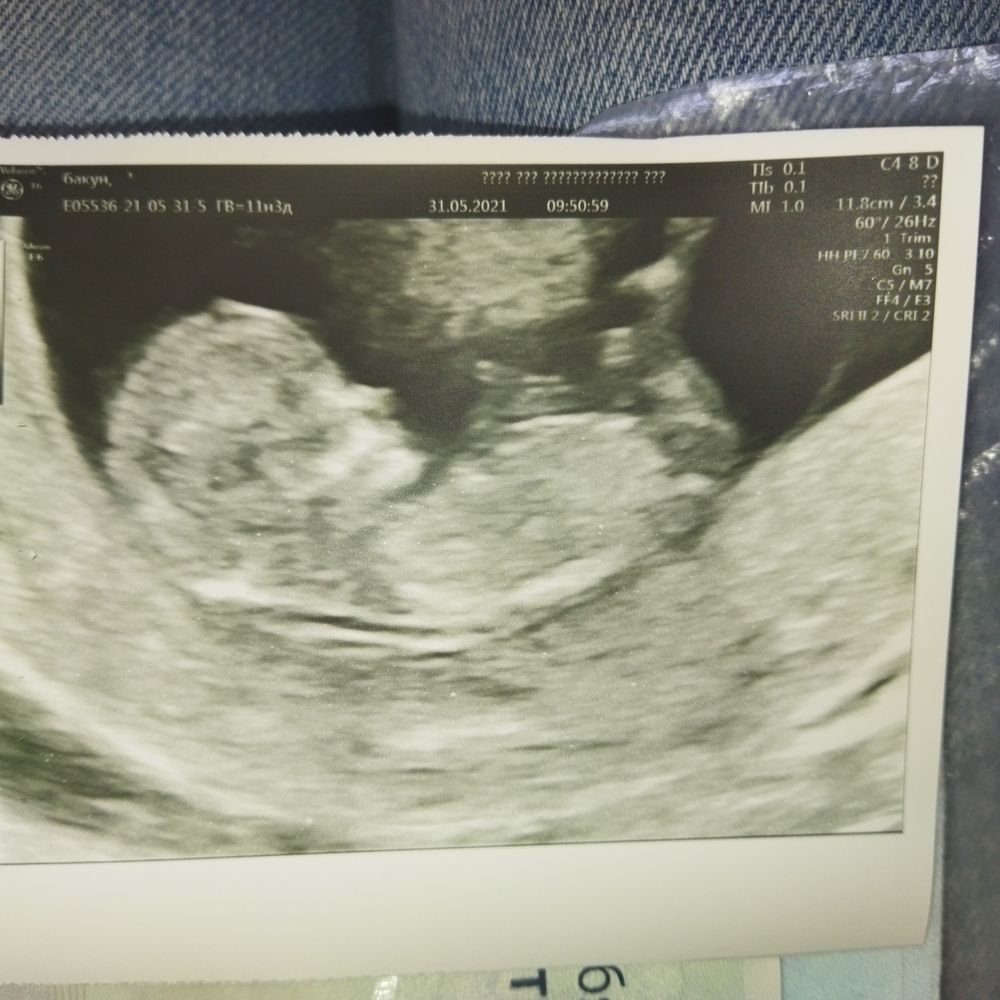

Пол малыша

Нет бугорка. Так что пока просто ребенок.

На фото нет полового бугорка ,да и рано ещё .

По этому УЗИ не видно

На фото нет полового бугорка, и срок ещё совсем маленький, хотя бы в 13 недель надо смотреть

На фото полового бугорка не видно.

Если это половой бугорок, то девочка

Пол ребёнка Пол на 1ом скрининге... Кого вы видите?